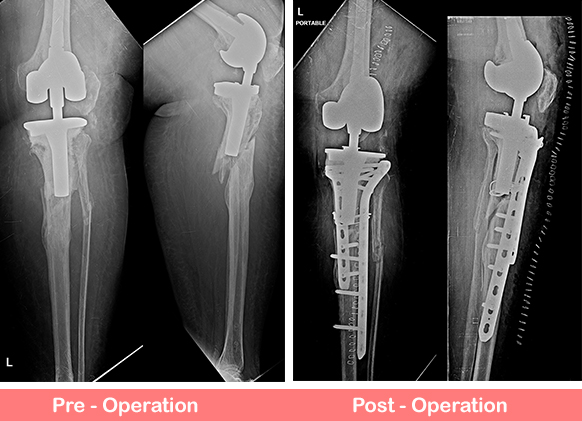

Pre-surgery Planning:

- Imaging: A series of X-rays, CT scans, or MRIs are often taken to assess the condition of the existing knee prosthesis, surrounding bone, and any complications (such as infection or fractures).

- Bone Assessment: The surgeon will evaluate the bone quality and may use techniques such as bone grafting to help reconstruct areas that have lost bone mass.

Surgical Process:

- The surgeon removes the old components of the knee replacement, which may involve cutting through scar tissue and sometimes dealing with damaged or weak bone. If the original components were cemented, the surgeon may need to carefully remove the cement as well.

- After the damaged components are removed, the surgeon prepares the bone and soft tissue for the new components. New prostheses are then inserted, which may include the femoral component, tibial component, and patellar component, depending on the extent of the damage.

- If bone loss or deformity is present, bone grafts, spacers, or custom implants may be used.